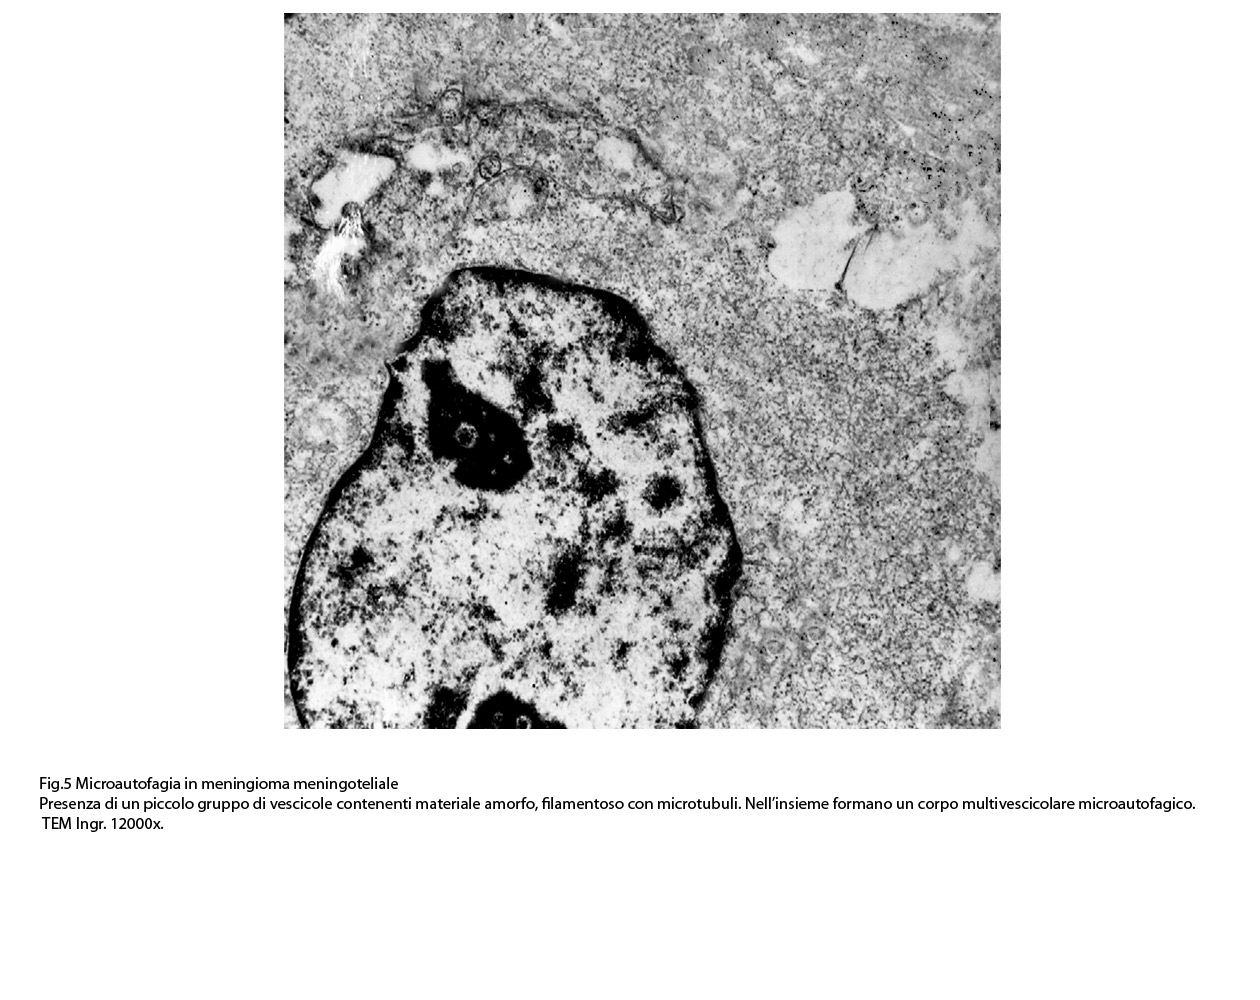

1) MICROAUTOFAGIA

Nel citosol si repertano vescicole di piccole dimensioni delimitate da una membrana di contorno a mono strato. Il loro lume è occupato da materiale amorfo e da corti filamenti distribuiti in modo disordinato.

Queste vescicole sono distribuite in modo irregolare, anzi casuale e si ritrovano ad essere isolate o riunite in piccoli aggregati formando un’immagine definita corpi multivescicolari.

Frequentemente questi focolai si ritrovano commisti ad altri aventi i caratteri della macroautofagia e sono in parte da questi mascherati. A parte questi particolari reperti,il citosol è occupato da numerosi mitocondri di piccole dimensioni e di forma rotondeggiante e di aspetto compatto,da ergastoplasma rugoso e da quote ben rappresentate di reticolo endoplasmico e di strutture lisosomiali.